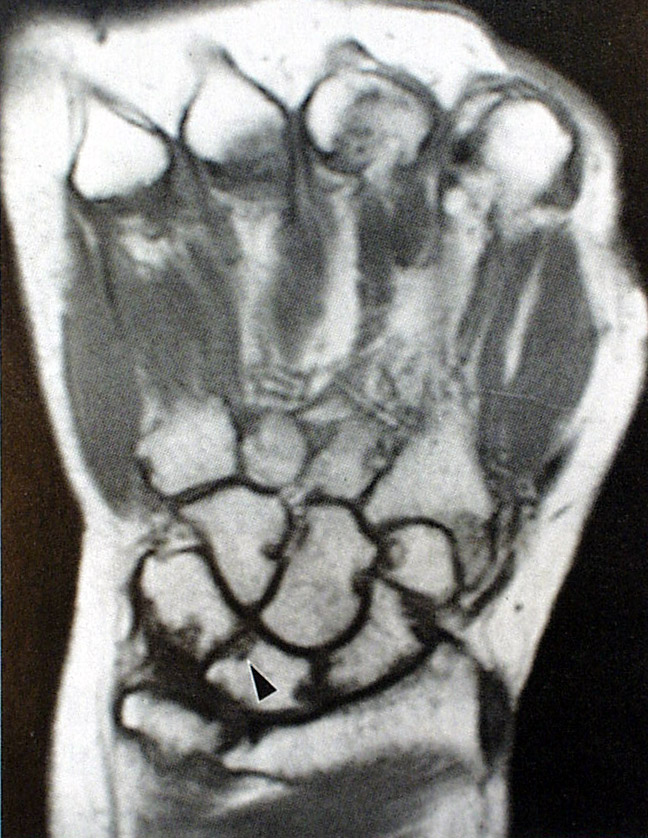

滑膜增厚、毛糙,并见多处腕骨有软骨下骨吸收。

关节肿胀,骨质疏松,间隙变窄,指间关节、腕骨侵蚀破坏,指间关节向尺侧偏斜畸形

晚期改变 :关节挛缩变形,关节半脱位,手指向尺侧偏斜畸形